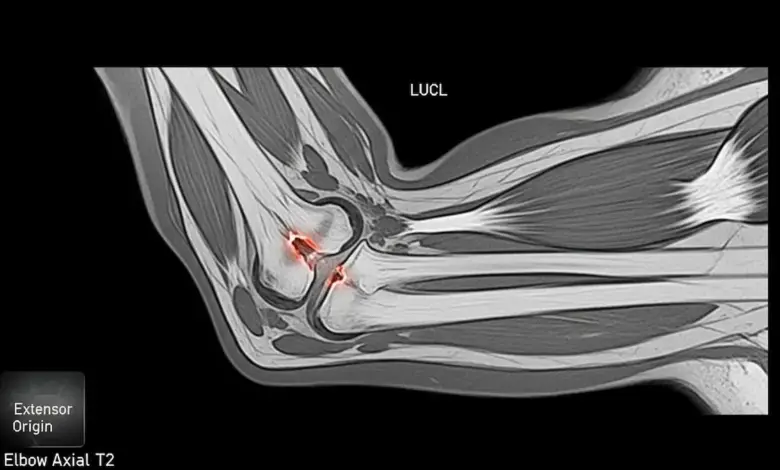

- A ressonância magnética permite visualizar o ligamento, identificar rupturas parciais ou completas e avaliar estruturas adjacentes.

- Em casos selecionados, a artro-RM melhora a sensibilidade do exame.